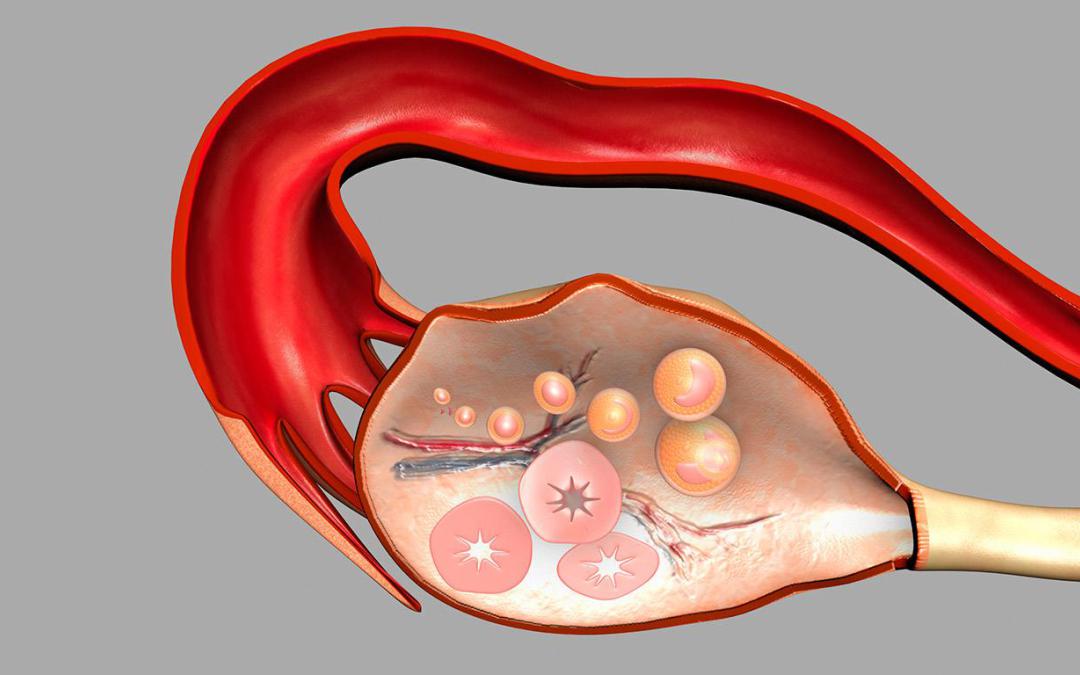

Созревание фолликула в яичнике: этапы и процессы